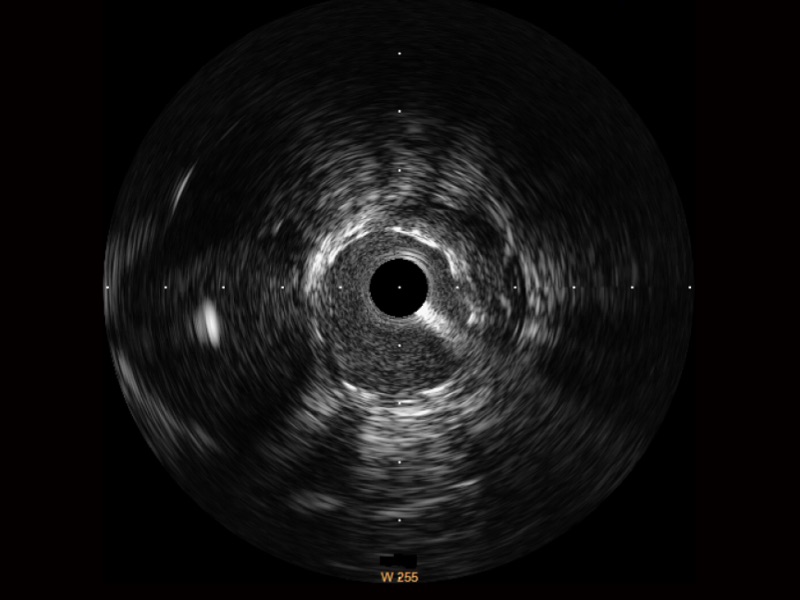

传统IVUS图像

对比传统IVUS导管成像,玖鼎集团宽频IVUS图像的近场支架梁显影更细腻,远场中膜外血管仍清晰可辨,兼顾远中近,兼顾分辨力与穿透深度